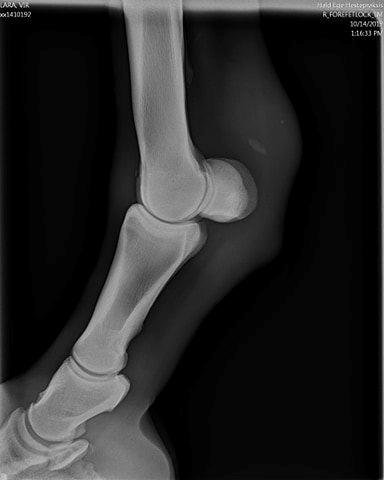

Hej folks, jeg har dette røntgenbillede af min hoppe. hun er blevet brugt for halvanden år siden 3x5 gange ugentligt på rideskole og er blevet totalt overbelastet, resulterede i hun blev halt hver 3-4 uge, og stod så stille i en mdr, derefter fuld træning igen som rideskoler nu for det meste gør uden genoptræning.

Men der er jo denne bugle, og det ligner ikke en knogle. De sagde først ved rideskolens tjek med dyrlæge, at det var mus, men det var det så ikke, så siger næste dyrlæge en forkalkning, men det tvivler vi også på. Hvad vil i sige?

Hvis det er den lille splint, der "svævet" ude i vævet, så gætter jeg på, at det er en forkalkning i senevæv.

Ved langvarig belastning kan der udfældes knogle. Ses fx på rtg hos mennesker med hælspore.